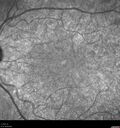

Ocular Lymphoma - Initially presented like auto-immune retinopathy280 views43 year old man: initial presentation - The vision in the left eye is blurry and opaque for about 2 weeks. In the central of the vision, when he covers the right eye, in the center of the left eye there is a film with a light in the middle. This has never happened before. He has not been sick for the last few months. A few weeks ago he saw waves on the floor when looking down but that has gone away. Since the vision loss started the vision has not changed much. The central vision is not getting better. Â

Labs normal. One positive antiretinal antibody - Arrestin

VA improved over 2 months to normal. Then the patient had 2 more episodes of self-limited vision loss (no treatment). Then 2 years later he presented with a diagnosis of CNS lymphoma and later developed subretinal deposits (last images)Oct 25, 2021